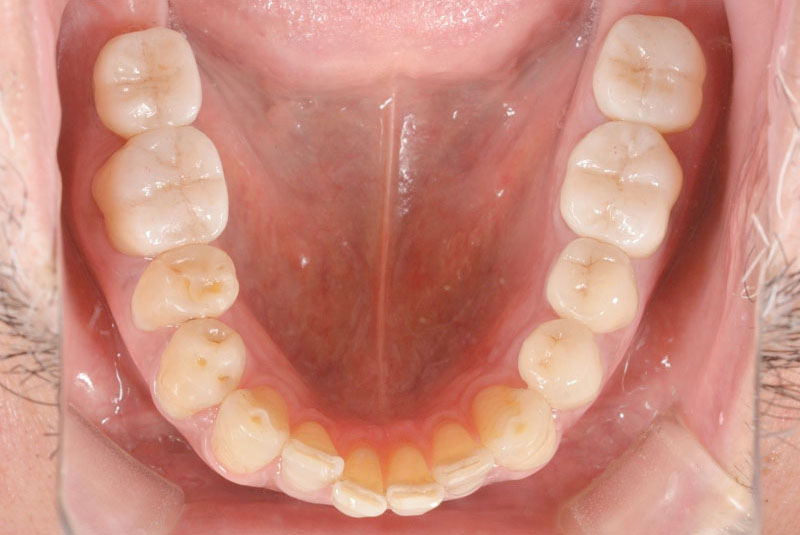

多数歯欠損のインプラント(サイナスリフト・GBR併用)

- 患者

- 50代男性

- 主訴

- インプラントができないかどうか相談。

できるだけきれいにしたい。

- 治療経過

- 前医にて上顎部分入れ歯を装着、下顎の奥歯を抜歯した状態で来院されました。また下顎の両側の臼歯の抜歯が必要と診断されたとのことでした。前医にインプラントを相談したが下顎はできるが、上顎は骨がないことを理由にインプラント不可能と診断され当院受診されました。診断の結果、下顎臼歯は保存可能、上顎臼歯部は左右上顎洞に対する骨造成(サイナスリフト)、前歯部はGBRにて骨造成を行い、インプラント埋入を行いました。

サイナスリフトはかなり専門性の高い外科処置であるため対応できる歯科医師は限られます。そのためショートインプラントや傾斜埋入で対応されることも多いですが、患者さんの年齢や希望を伺いながら当院では必要であれば積極的に行っております。その他不良補綴物の除去、根管治療、虫歯治療を行い全顎に対して審美的修復を行い治療終了までに2年を要しました。ちなみに当院では1本も抜歯は行いませんでした。保存できる歯と抜歯の必要な歯をしっかり診断することも必要です。